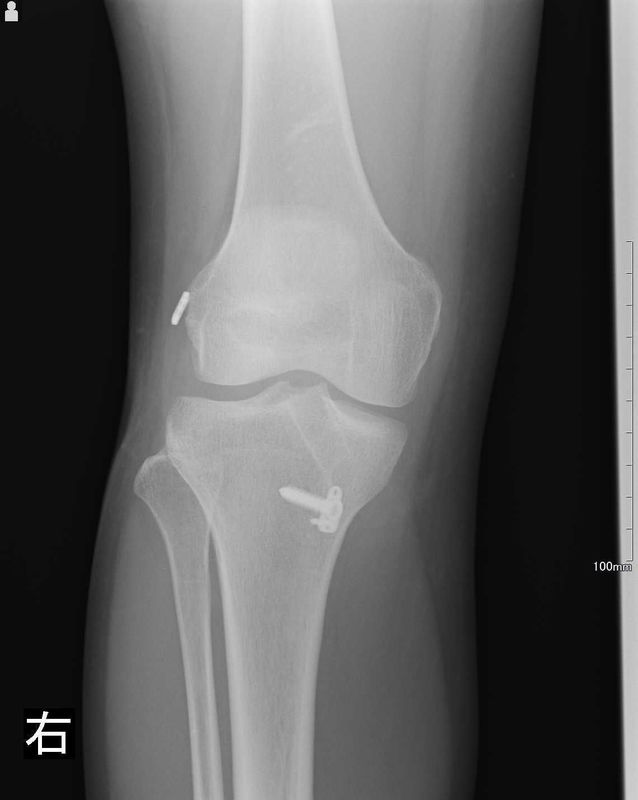

レントゲン所見

| 手術前 | 手術後 |

![]() |

| 骨傷・変形はない | 異常なし |